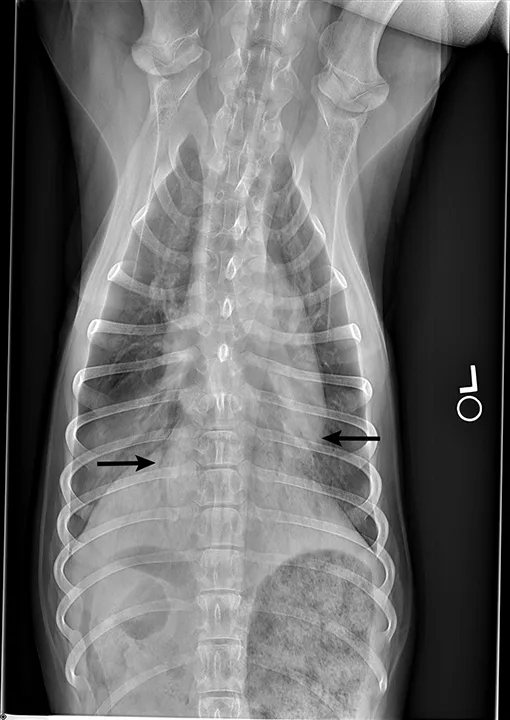

Blood pressure was decreased (85 mm Hg) on Doppler ultrasound. Oxygen saturation was initially 92% but increased to 98% with flow-by oxygen supplementation via mask (4 L/minute). Initial blood work showed mild hyperlactatemia (3.1 mmol/L; reference range, 0-2.5 mmol/L), packed cell volume of 54%, and total solids at 6.8 g/dL. Chest radiography was performed with oxygen supplementation and revealed a moderate to severe caudodorsal interstitial to alveolar lung pattern (Figures 1 and 2).

Radiographs showing caudodorsal alveolar pattern consistent with noncardiogenic pulmonary edema (arrows). Edema is caudodorsal and bilateral. The heart size is normal, and there is no elevation of the airways that would indicate left-sided heart enlargement. Sternal contact of the heart, which might suggest right-sided heart enlargement, is minimal.